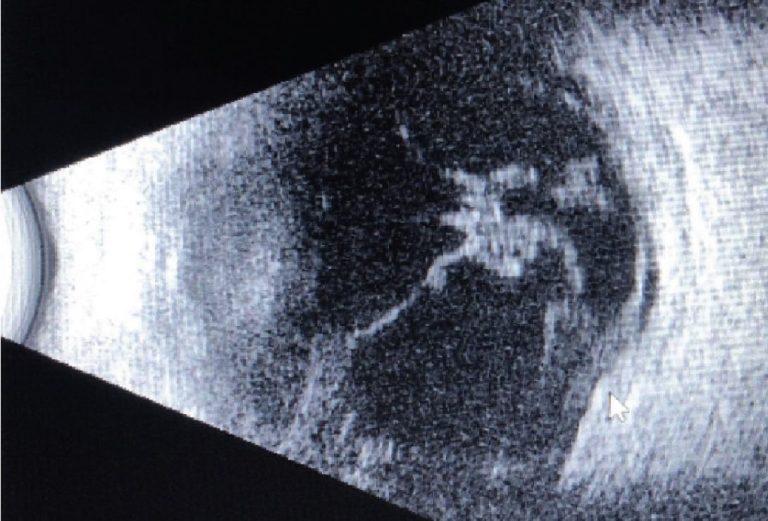

En el examen clínico, se observó un gran defecto epitelial que medía 10 mm x 6 mm, con un área de necrosis coagulativa central y extensión a la esclerótica superior. El A/C era profundo y estaba formado por un denso hipopión. La ecografía B-scan realizada mostró vitritis, lo que era preocupante para endoftalmitis.

Caso 1. Ecografía B-scan tomada en el examen preoperatorio. Aún se observan restos vítreos, desde la presentación inicial.